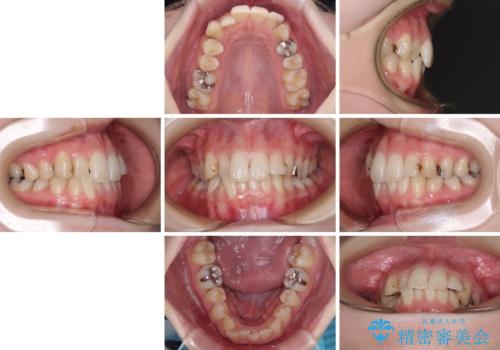

- 前歯のデコボコをクロスバイトを気にして来院された患者様です。

上顎骨の横幅が狭く、上下ともに内側に倒れ込んだ混み合った歯列となっていました。

急速拡大装置により上顎骨を側方に拡大し、ワイヤー装置により歯列を整えることとしました。

矯正治療後には、目立つ銀歯と隣接するむし歯をセラミックインレーにて修復治療することとしました。